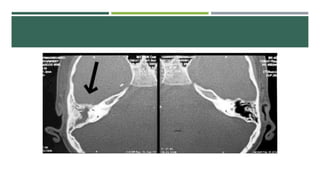

MASTOIDITIS

 Necrosis de las trabéculas Oseas

 Formación de absceso

 Puede evolucionar a periostitis y absceso subperiostico

 Mastoiditis aguda

 Dolor e Hipersensibilidad en apófisis mastoides

 Edema y eritema de tejidos blandos posauriculares

 Desplazamiento anteroinferior del pabellón auricular

 Realizar TC, Antibioticoterapia. Miringotomia, Mastoidectomia

MASTOIDITIS  Necrosis delas trabéculas Oseas  Formación de absceso  Puede evolucionar a periostitis y absceso subperiostico o infección intracraneal  Mastoiditis aguda  Dolor e Hipersensibilidad en apófisis mastoides  Edema y eritema de tejidos blandos posauriculares  Desplazamiento anteroinferior del pabellón auricular  Absceso de Bezold  Absceso de Citelli  Realizar TC, Antibioticoterapia. Miringotomia, Mastoidectomia